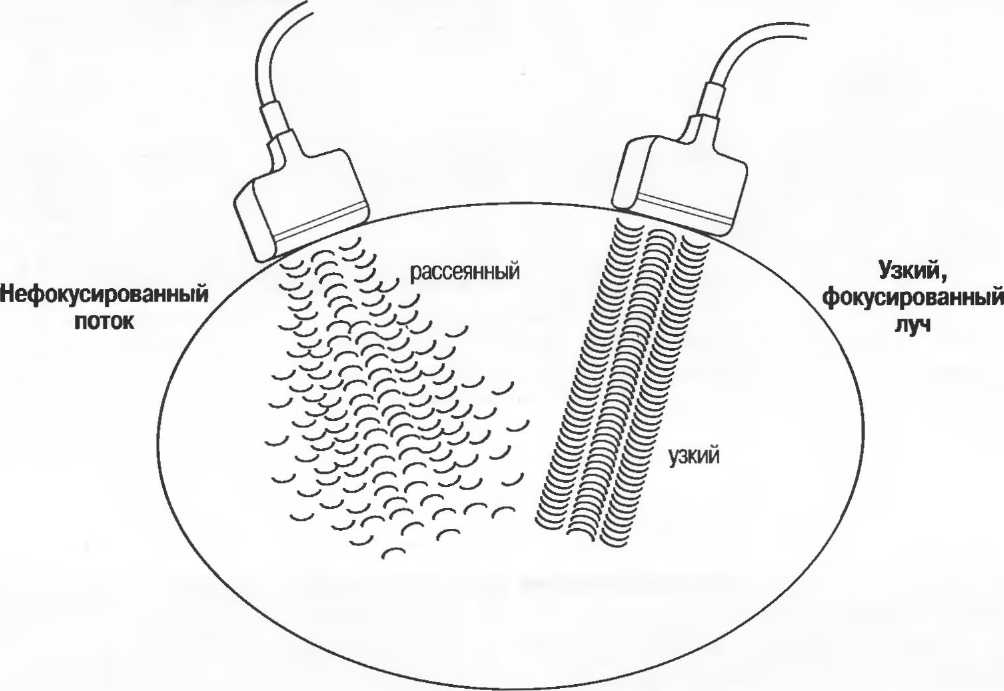

Фокусировка

Фокусировка может осуществляться линзами, зеркалами или электронным путем в многоэлементных датчиках. Как узко направленный пучок света более четко показывает объект, чем более рассеянный, несфокусированный поток, так и фокусированный ультразвук дает более тонкий срез ткани, в результате чего изображение получается более детальным. Для получения наилучшего результата необходима фокусировка на той глубине, которая наилучшим способом соответствует поставленной клинической задаче. Для аппаратов общего назначения это означает использование специальных датчиков для различных целей и, при необходимости, использование программы фокусировки аппарата (рис. 3).

Различные варианты фокусировки

Многие трансдьюсеры имеют фиксированный фокус. Многоэлементные трансдьюсеры, например линейные или конвексные, а также аннулярные секторные имеют электронно задаваемое фокусное расстояние, устанавливаемое на требуемую глубину. Тем не менее многие трансдьюсеры имеют фиксированное фокусное расстояние: только аннулярные секторные датчики имеют электронную фокусировку во всех плоскостях. Регулирование фокусировки обеспечивает узкий акустический поток и более тонкую плоскость среза: это дает более высокую разрешающую способность и более четкое изображение с большей информацией.

Фокусировка ультразвукового луча

Так как органы и ткани тела, которые подлежат исследованию, находятся на разной глубине, идеально было бы настраивать фокус датчика (с. 10 и 20). Если фокусное расстояние фиксировано, то выбирается наиболее подходящий датчик для данного исследования. Выбор оптимального датчика описывается в каждом разделе руководства.